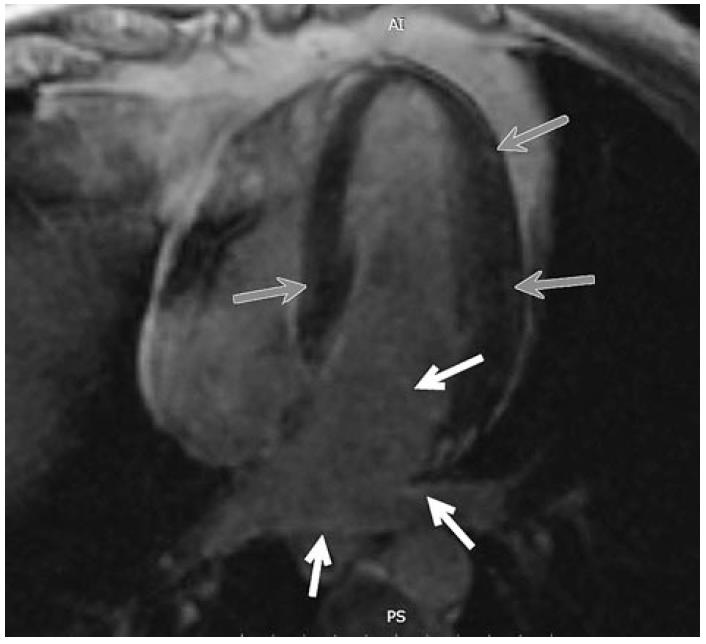

Для определения фиброза миокарда при МРТ оценивалось накопление контрастного вещества (рис. 2). Диффузное или локальное накопление контрастного вещества выявлено у большинства пациентов – в 11 (61%) случаях, у 4 женщин и 7 мужчин. Накопление контрастного вещества преимущественно в области эндокарда, митрального и трикуспидального клапанов наблюдалось в 8 случаях, у 3 пациентов отмечено сочетание диффузного и очагового накопления, у 1 пациента определено локальное накопление и у 7 пациентов не наблюдалось накопления контрастного вещества в отсроченную фазу. Достоверных различий между пациентами с наличием и отсутствием накопления контрастного вещества при МРТ по возрасту, длительности заболевания, ИМТ, уровню тиреоидных гормонов, СТГ, ИФР-1, частоте ремиссии, получаемой терапии аналогами соматостатина не выявлено.

Рис. 2. МРТ сердца пациента с НРПС при акромегалии. Серыми стрелками указано диффузно-очаговое накопление контрастного препарата боковой стенкой ЛЖ, белыми стрелками – диффузное накопления контрастного препарата эндокардом левого предсердия и клапанов).